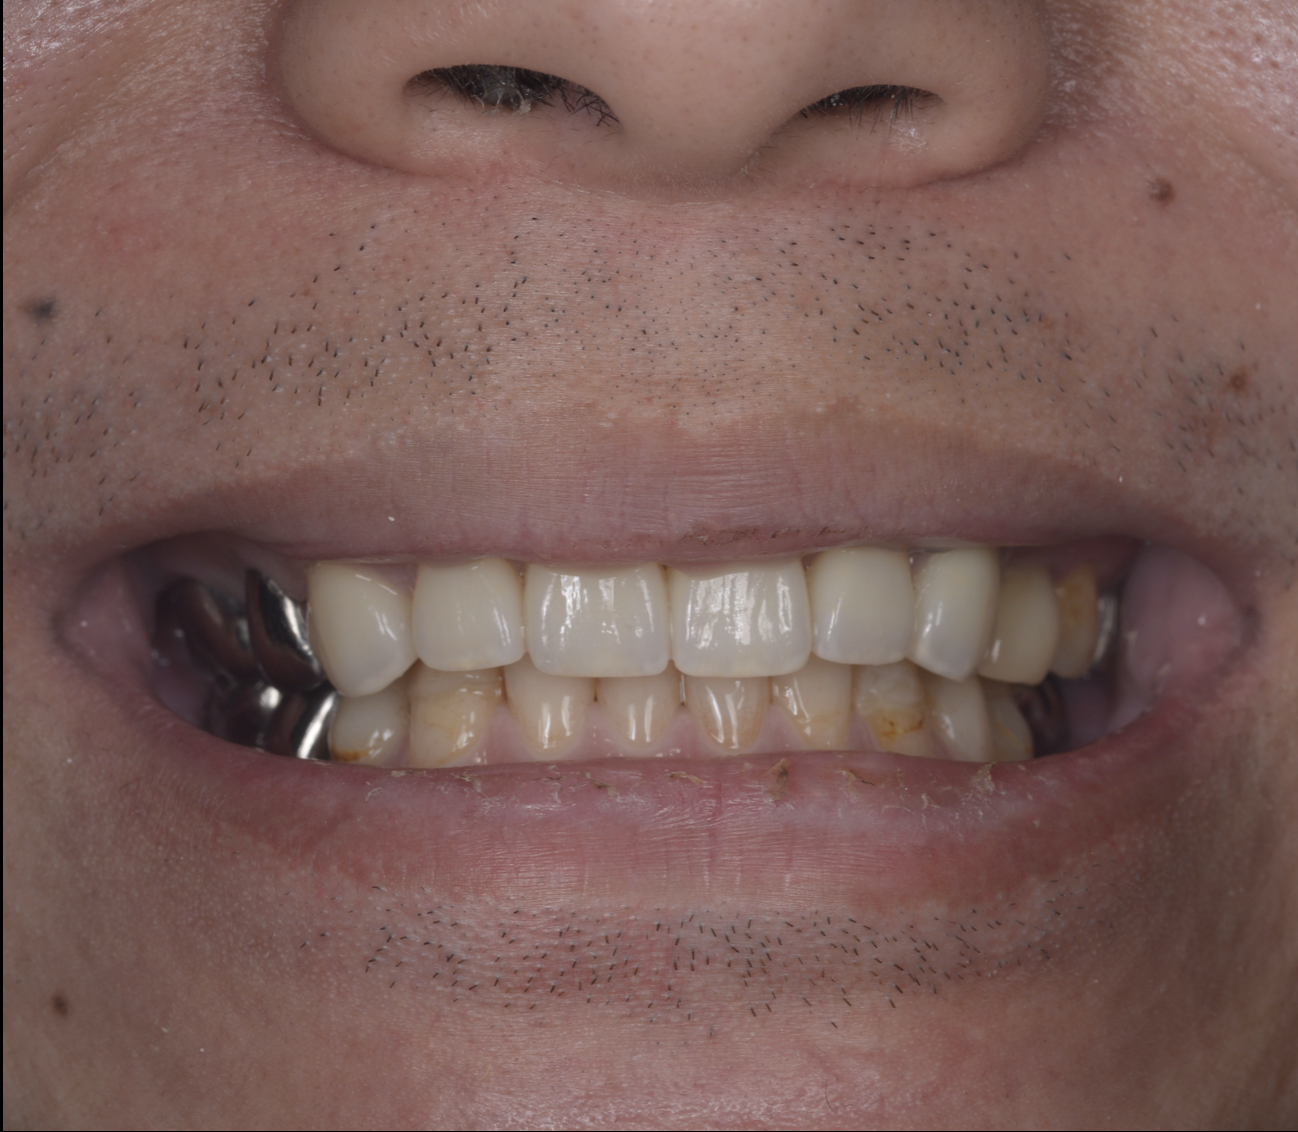

- 6.8 [20代男性]歯が折れた[歯の移植]